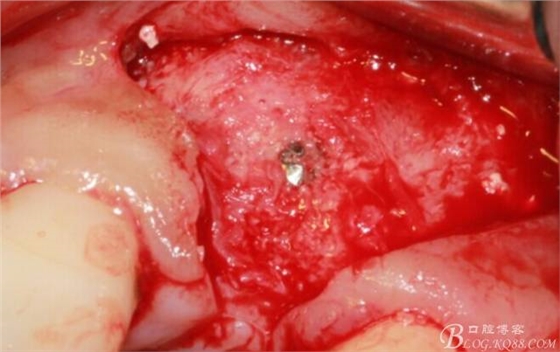

翻開(kāi)后驚喜的發(fā)現(xiàn),術(shù)區(qū)成骨非常好,去除部分骨才暴露那顆長(zhǎng)鈦釘。

取出影響種植入路的長(zhǎng)鈦釘。

擴(kuò)孔。